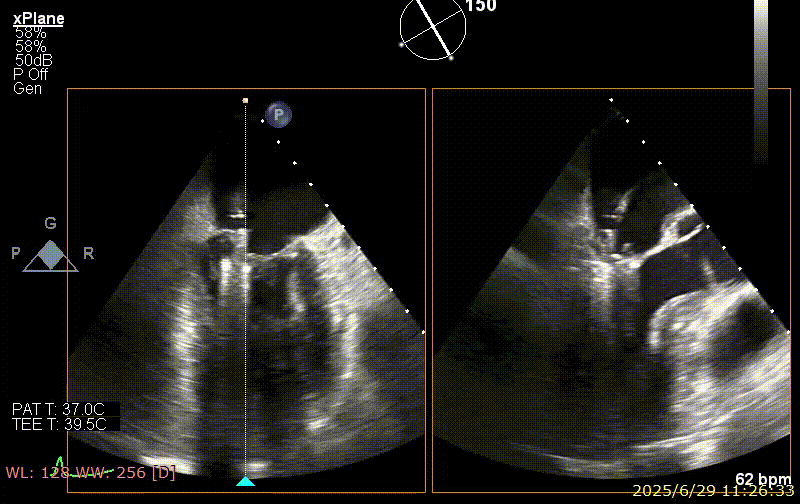

术前超声

患者术前 TEE 可见 P3 区脱垂二尖瓣环前后径(AP)约 37 mm,CC 径约 41 mm,瓣叶无明显钙化及裂隙,后瓣瓣尖探及一长约 9 mm 短带样回声漂附,二尖瓣口面积约 5.3 cm²。

经我院心脏超声检查提示:左房室增大伴二尖瓣后瓣脱垂(P3 区,腱索断裂)并重度关闭不全(Carpentier IIb 型,反流分级 4+);符合高血压性心脏病改变;少至中等量心包积液;左室舒张功能降低,收缩功能测定在正常范围并呈假性高排表现。